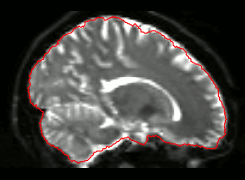

- Images, masks

- Itksnap

- FSLview

- Freeview